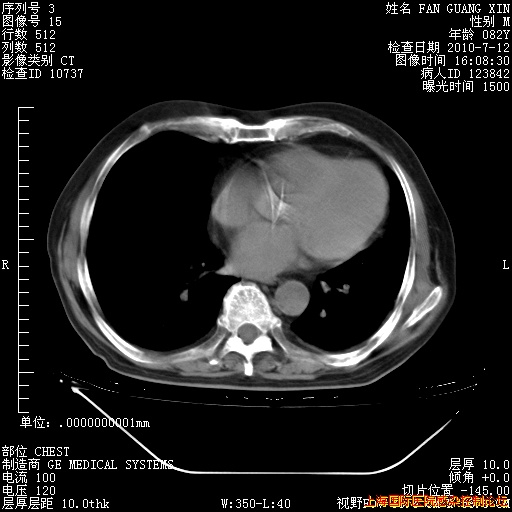

6月12日纵膈窗

今天复查CT

今天CT

整整相隔30天的肺部CT好像有所好转啊。甲强龙减量第3天,需要观察体温。